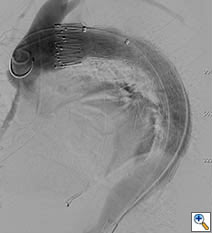

A 49-year-old woman with a history of hypertension and smoking presented to an outside hospital with sudden onset chest pain and hypotension. Computed Tomography/ Angiography (CTA) of the chest and abdomen revealed a type A aortic dissection extending from the ascending aorta to the left common iliac artery. (Figure 1) Of note, there was a significant pericardial effusion and left pleural effusion. Due to her hypotension and tamponade physiology, the patient was rapidly intubated followed by unsuccessful pericardiocentesis. The patient was then transferred to our institution for emergent dissection repair.

Figure 1a-e. Computed Tomography/Angiography (CTA) at

presentation demonstrating a type A aortic dissection.

Figure 1a. Axial CT at level of the pulmonary artery. The false lumen in the ascending aorta (white arrow) has minimal flow.

Figure 1b.

Figures 1b-d. Axial CT cuts demonstrating the dissection continuing into the left common iliac artery.

Figure 1e. Oblique sagittal CT reconstruction demonstrates the Type A dissection is complex with multiple fenestrations in the abdomen. Note bovine arch anatomy.